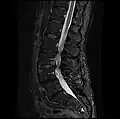

MRI lumbar spine with degeneration, post-hemilaminectomy L4-5 (sagittal FAST STIR)- MRI lumbar spine post-hemilaminectomy (sagittal T2 FRFSE)